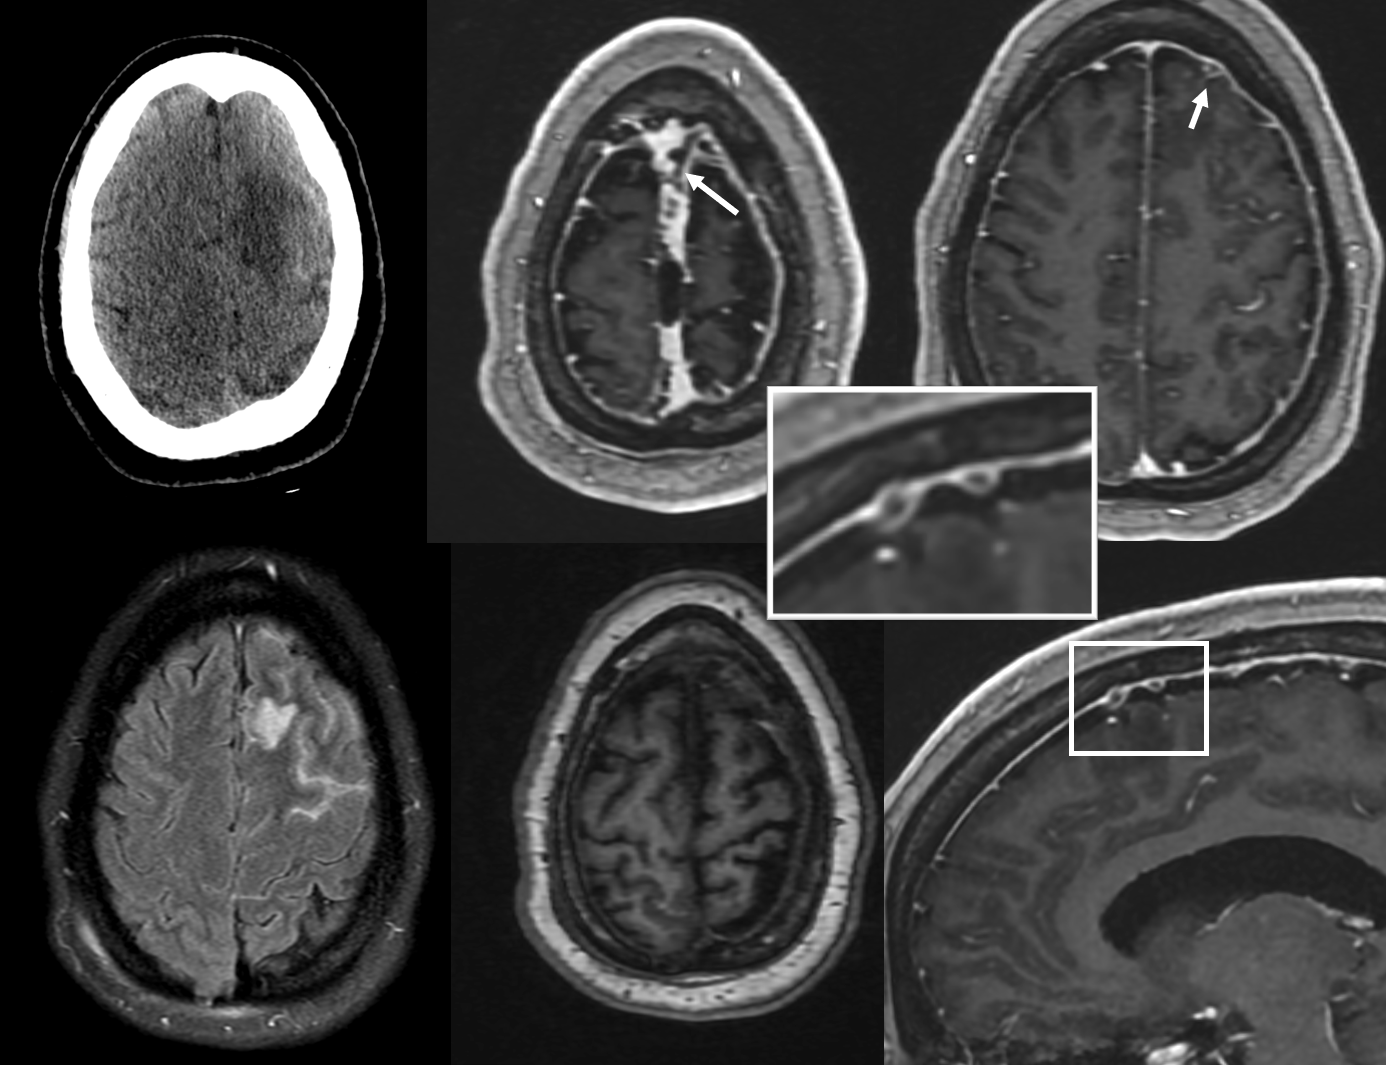

NOT ALWAYS ASYMPTOMATIC! — here is left frontal convexity cortical venous thrombosis in veins emptying into SSS at level of giant granulation. Very likely related. Granulation is in middle upper row image. Full case (angios etc) here.

Sagittal Sinus Thrombosis — collaterals.

All of the above anatomic knowledge can become very useful in evaluation of venous thrombosis. Numerous collateral pathways develop in this setting attempting to compensate for the loss. The most dramatic cases usually involve the largest channel — the superior sagittal sinus. In this case, a man presented with what initially was thought to be vasculitis-related brain hemorrhage. Subsequent workup led to an angiogram, where sagittal sinus thrombosis with extensive trans-cerebral and trans-osseous emissary vein collateral channels was seen. In retrospect, these findings were present on the patient’s earlier contrast MRI. “Venovibe” or other contrast-enhanced MR venograms can very sensitive, particularly when interpreted with the appropriate index of suspicion. Noncontrast 2-D time of flight MRV I consider to be next to useless as a problem-solving technique. Any thin-slice postcontrast T1 study is vastly superior.